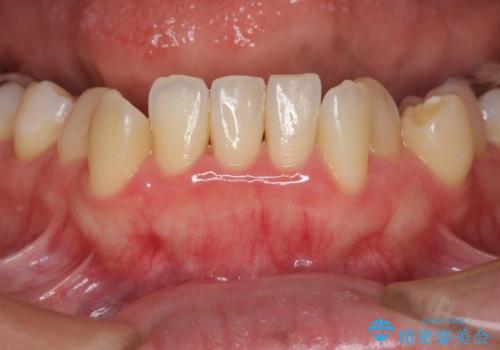

初診時、下顎前歯にびっしりとついていた歯石を除去することで歯肉の発赤・腫脹は治まり健康な状態になることができました。